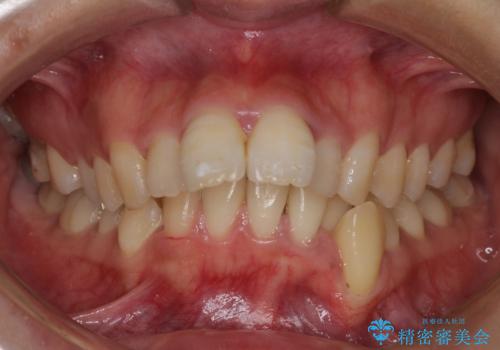

- 口元がひどく突出するくらいの上顎前突を気にして来院された患者様です。

舌の突出癖が顕著で、上顎歯列は完全なV字型となっている状態でした。

下顎歯列にも八重歯があり、上下左右の第一小臼歯4本を抜歯して、ワイヤー装置にて矯正治療を行うこととしました。